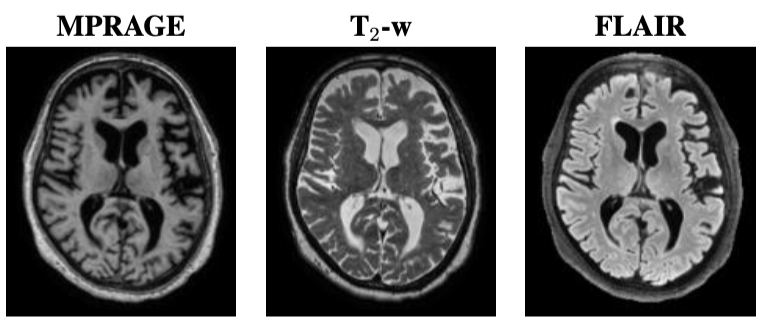

Our training dataset consists of four brain MR image contrasts that have been acquired for 23 subjects. These contrasts include MPRAGE, FGATIR, T2-w, and FLAIR. Example images of these four contrasts are shown in Fig. 3. The MPRAGE and FGATIR images are acquired with the same imaging parameters (TR = 4,000ms, echo time = 3.37ms, flip angle = 66^{\circ}, and magnetic field strength = 3 Telsa) except for their inversion times (TIs), which are TI = 1,400ms for the MPRAGE and TI = 400ms for the FGATIR. For training the networks described in Sec. 2.5, we used a 5-fold cross validation. We divided our 23 subjects into 14 training subjects, 4 validation subjects, and 5 testing subjects. For the 5th-fold, only 3 testing subjects were used to allow each subject to be tested once. The validation set was used to monitor the loss during training and for early stopping.

Refer to caption

Figure 3: Example images from the same subject, from left to right, are the MPRAGE, FGATIR, T2-w, and FLAIR.